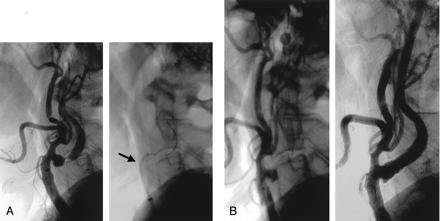

Angiographically visible vascular dissection of the ICA at the occlusion balloon site occurred in 18 patients (5.9%), with no associated neurologic events (Fig 5). In 13 of these patients, the dissection was notable for retention of contrast medium in the vessel wall; in three, the dissection was notable for a small non–flow-limiting dissection flap; and in one patient, the dissection was characterized by deep disruption of the vessel wall with 50% non–flow-limiting stenosis. One patient had a significant dissection that resulted in an occlusion of the ICA, with no associated neurologic deficit. This was successfully recanalized and a stent was placed.

Dissection caused by occlusion balloon in a 79-year-old man.

A, Right carotid angiogram shows near occlusion of the ICA.

B, Angiogram shows that the temporary occlusion balloon is inflated. Predilation was performed with a 4 × 40-mm balloon.

C, Follow-up angiogram obtained after carotid artery stent placement shows significant dissection at the level of the previously placed occlusion balloon. Satisfactory result of carotid artery stent placement with a 9 × 30-mm stent (Medtronic AVE).

D, Follow-up angiogram after placement of a 4 × 23-mm coronary stent in the dissected segment of the ICA.

It is important to distinguish spasm from dissection (Fig 5). Dissection at the level of the occlusion balloon can be caused by oversizing the balloon or by not having the occlusion balloon well stabilized throughout the procedure (ie, by its craniocaudal motion). The most common cause of distal ICA dissection is oversizing the occlusion balloon. The diameter of the ICA at the level of the intended balloon occlusion can be measured at the beginning of the procedure. However, this measurement is not reliable for achieving a complete occlusion of the ICA throughout the procedure. The size of the ICA varies with blood flow. In a severely stenosed ICA, the vessel is partially collapsed and may significantly expand after predilation and stent placement. An appropriately sized occlusion balloon at the beginning of the procedure may become nonocclusive during the procedure. Ideally, the occlusion balloon should be more compliant than the present system and change in size and shape depending on the vessel diameter without exerting too much pressure on the vessel wall. The new-generation system is more flexible with the possibility of inflating the occlusion balloon 3–6 mm by 0.5-mm increments. The occlusion balloon can also be inflated in the petrous segment of the ICA. Although at this level the ICA cannot be distended, owing to its confinement within bone, this location of the occlusion balloon significantly elongates the occluded segment of the ICA from which the debris has to be aspirated and may decrease the efficacy of the system. In the presence of significant tortuosity of the ICA, this location would also be inconvenient for advancement of the Export aspiration catheter. At the end of the stent placement procedure, it is important to carefully examine the neck segment of the ICA at which the occlusion balloon was inflated. This segment of the ICA can be easily missed on the follow-up angiograms obtained after the procedure, as it is located at the level not included on the exposure of the bifurcation and excluded on the intracranial study.